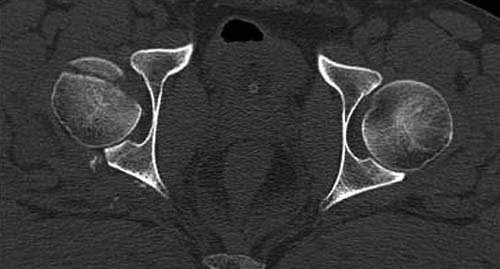

Представлены несколько вариантов фиксации: первый случай перелом головки с задним краем, операция из заднего доступа Кохер, а второй случай изолированный перелом головки - из трохантерного доступа.